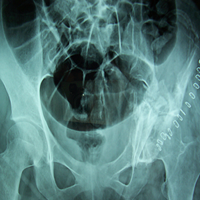

Case:4 GCT Acetabulum

Pre-Op